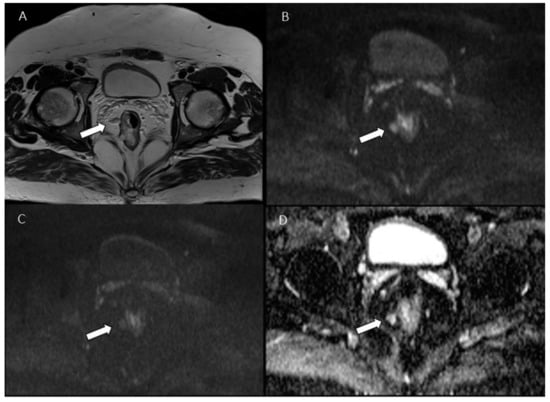

- Armbruster, M.; D’Anastasi, M.; Holzner, V.; Kreis, M.E.; Dietrich, O.; Brandlhuber, B.; Graser, A.; Brandlhuber, M. Improved Detection of a Tumorous Involvement of the Mesorectal Fascia and Locoregional Lymph Nodes in Locally Advanced Rectal Cancer Using DCE-MRI. Int. J. Color. Dis. 2018, 33, 901–909. [Google Scholar] [CrossRef]

- Grøvik, E.; Redalen, K.R.; Storås, T.H.; Negård, A.; Holmedal, S.H.; Ree, A.H.; Meltzer, S.; Bjørnerud, A.; Gjesdal, K.-I. Dynamic Multi-Echo DCE- and DSC-MRI in Rectal Cancer: Low Primary Tumor K(Trans) and ΔR2* Peak Are Significantly Associated with Lymph Node Metastasis. J. Magn. Reson. Imaging 2016, 46, 194–206. [Google Scholar] [CrossRef] [Green Version]

- Yu, X.; Wen, L.; Hou, J.; Wang, H.; Lu, Q. Discrimination of Metastatic from Non-Metastatic Mesorectal Lymph Nodes in Rectal Cancer Using Quantitative Dynamic Contrast-Enhanced Magnetic Resonance Imaging. J. Huazhong Univ. Sci. Technol. Med. Sci. 2016, 36, 594–600. [Google Scholar] [CrossRef]